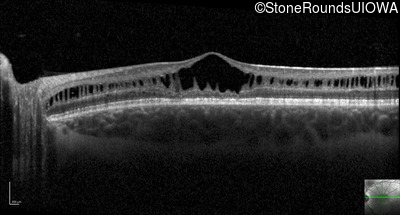

Optical Coherence Tomography - Right - 20/63 -2

Exemplar / OCT Stack

OCT Stack